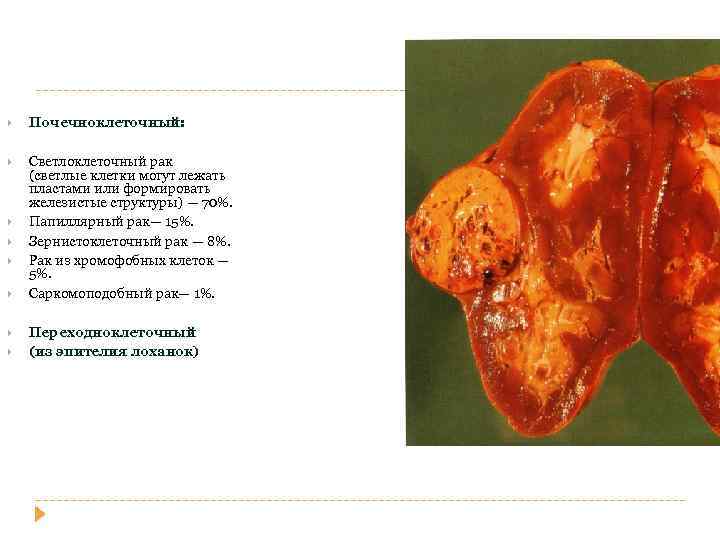

РАК ПОЧКИ Почечноклеточный: Светлоклеточный рак (светлые клетки могут лежать пластами или формировать железистые структуры) — 70%. Папиллярный рак— 15%. Зернистоклеточный рак — 8%. Рак из хромофобных клеток — 5%. Саркомоподобный рак— 1%. Переходноклеточный (из эпителия лоханок)